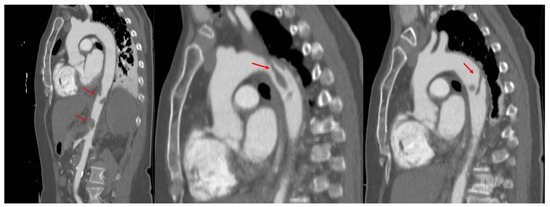

2. Case Presentation